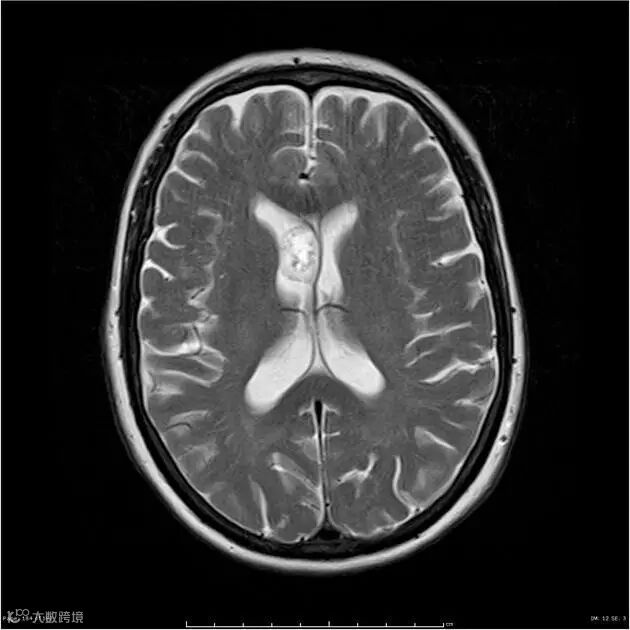

T2WI